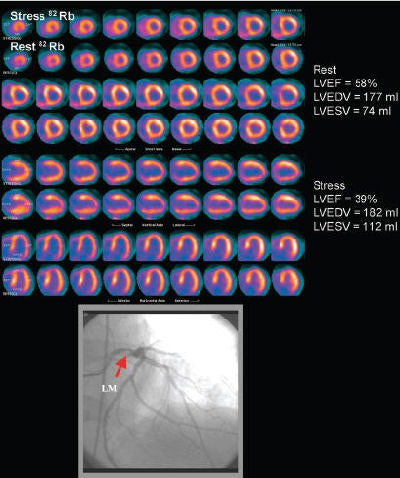

| Rest-stress myocardial perfusion PET/CT images in patient with severe angina demonstrate small region of moderate reversibility in middle and basal inferolateral walls. Gated study demonstrated significant decrease in LVEF during peak stress. Catheter coronary angiography demonstrated left dominant anatomy and severe left main coronary artery disease (bottom panel). Patient underwent coronary artery bypass surgery. LVEDV = left ventricular end-diastolic volume; LVESV = left ventricular end-systolic volume; LM = left main coronary artery. Reprinted with permission from "Value of Vasodilator Left Ventricular Ejection Fraction Reserve in Evaluation the Magnitude of Myocardium at Risk and the Extent of Angiographic Coronary Artery Disease: A 82Rb PET/CT Study;" Sharmila Dorbala, Divya Vangala, Uchechukwu Sampson, Atul Limaye, Raymond Kwong, and Marcelo F. Di Carli; March 2007, Journal of Nuclear Medicine. |

Using multiple logistic regression analysis, the scientists concluded that the only significant independent predictor of left main or three-vessel CAD was the LVEF reserve. They determined that for each unit increase in LVEF reserve, the odds of left main or three-vessel CAD decreased by 20%; for each unit decrease in LVEF reserve, the odds of left main or three-vessel CAD increased by 30%.

The researchers noted that obtaining an LVEF reserve parameter during a rest-stress Rb-82 PET exam is not difficult, and that the information it provides can exclude severe left main or three-vessel CAD with a high degree of certainty.